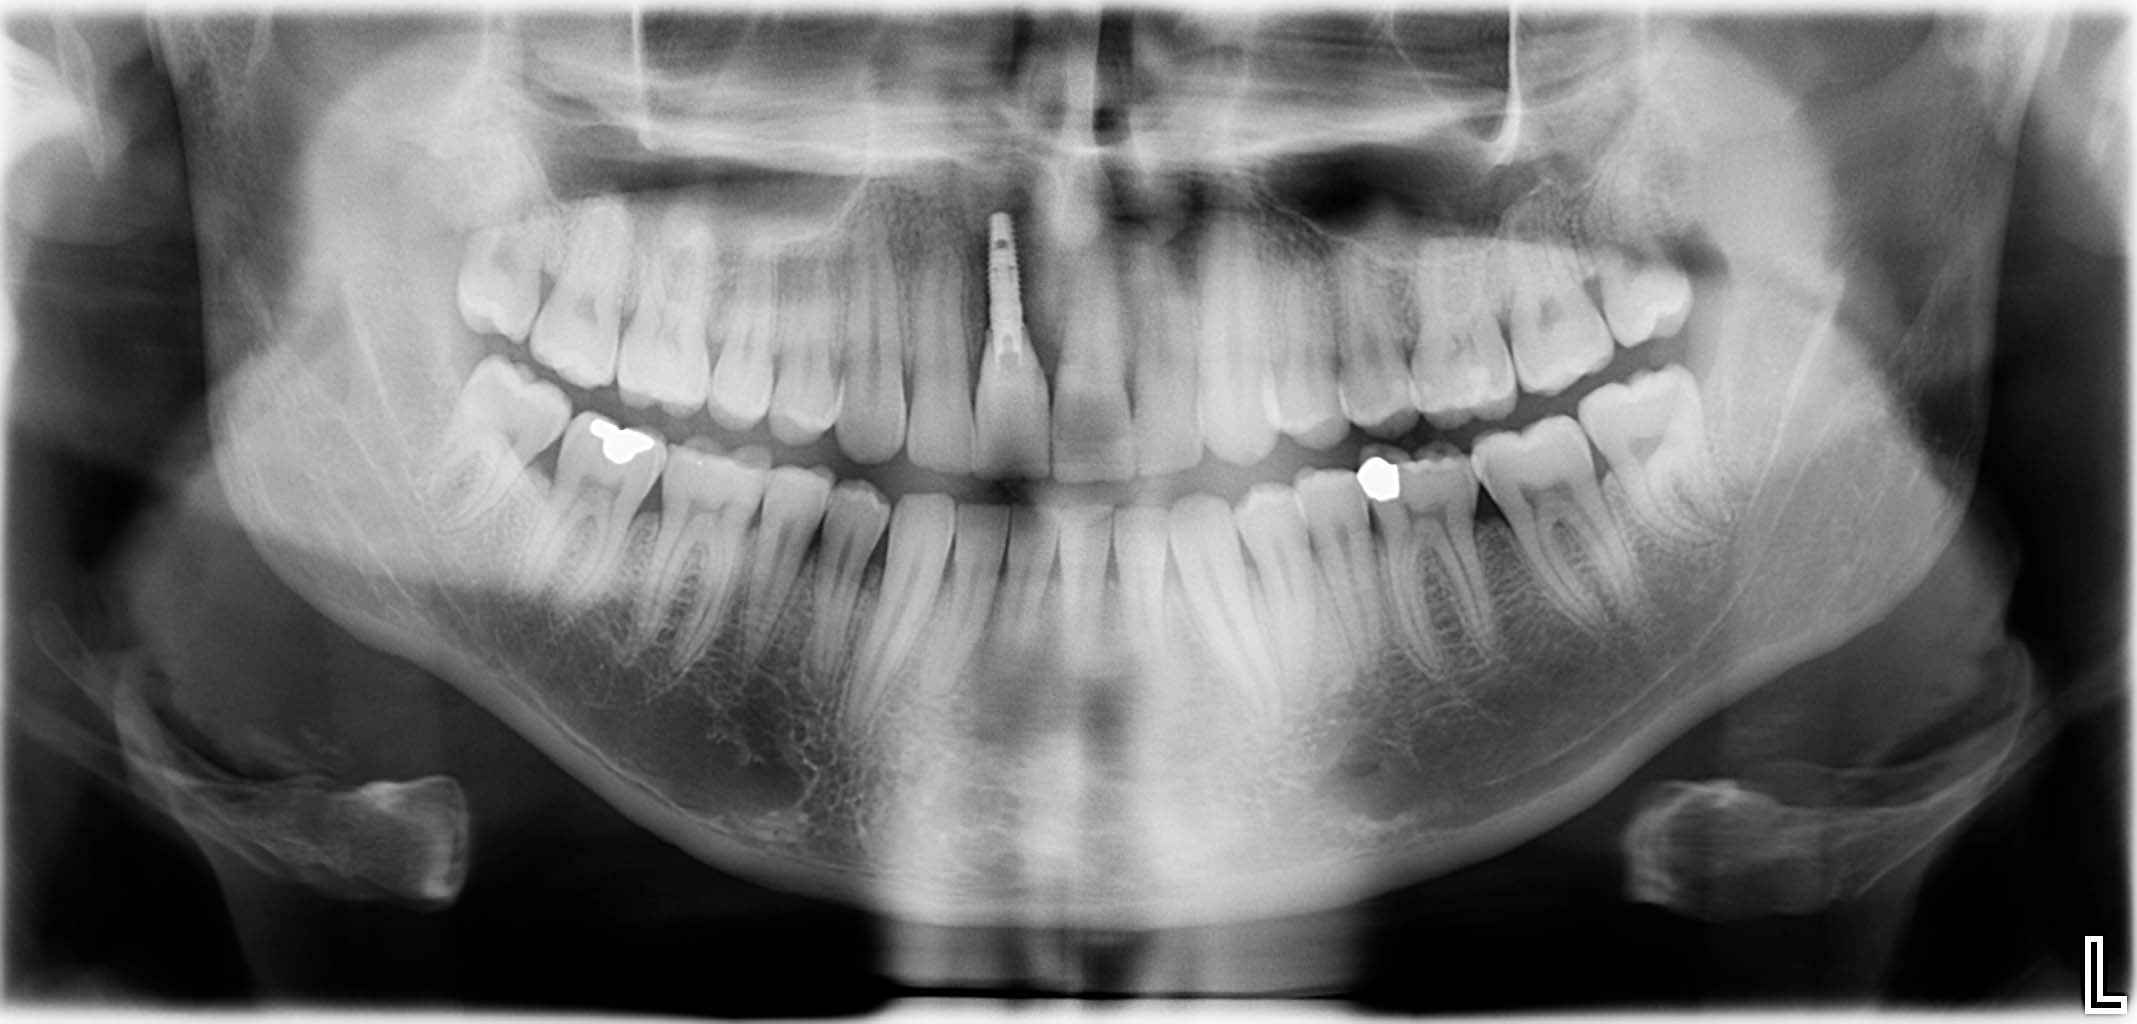

Ausgangssituation: Zahn 36 mit apikaler Beherdung, nicht erhaltungswürdig

Erfolgreich implantierte Patientenfälle (klinische Fotos)